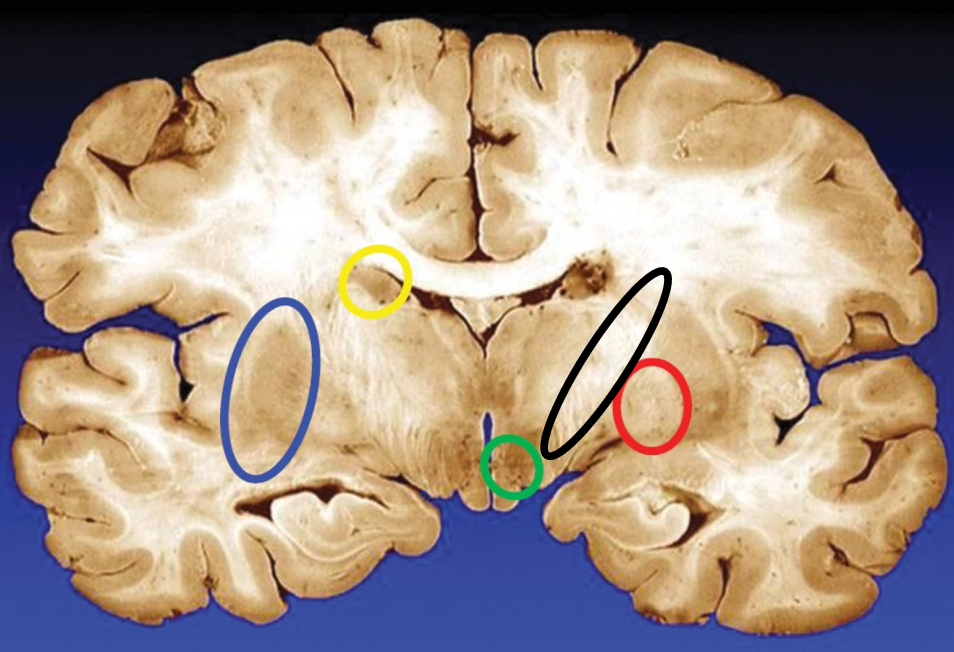

blue

putamen

yellow

caudate

green

subthalamic nuclei

black

internal capsule

red

globus pallidus

name the condition

Huntington’s (reduced caudate)